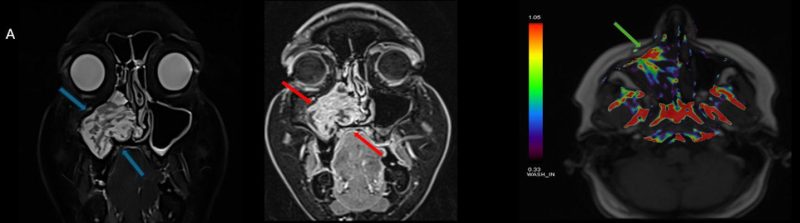

- A) Koronal T2 ağırlıklı görüntülerde sol maksiller sinüs lümenini dolduran, belirgin ‘convoluted’ (karmaşık-kıvrımlı) serebriform patern sergileyen lezyon (oklar), kontrastlı seride heterojen ve yoğun kontrastlanma göstermektedir (oklar). Perfüzyon incelemesinde pedinkülünde perfüzyon artışı gösterdiği, diğer kontrastlanan segmentlerin nispeten hipoperfüze olduğu görülmektedir (ok).

- B) BT incelemesinde maksiller sinüsün duvarları özellikle lateralde daha belirgin olmak üzere reaksiyonel kalınlaştığı izleniyor (oklar). DWI ve ADC haritasında lezyonda belirgin bir kısıtlılık görülmemektedir (oklar).

- MR incelemesinde sinonazal inverted papilloma tipik olarak T2 ve post-kontrast T1 serilerde ‘convoluted’ serebriform paternde heterojen sinyal ve kontrastlanma gösteren, pedinküler orijininde daha belirgin perfüzyon artışı sergileyen, genellikle difüzyon kısıtlaması izlenmeyen ve komşu sinüs duvarlarında ekspansiyona bağlı remodelinge yol açabilen benign ancak lokal agresif karakterde bir yumuşak doku kitlesi olarak izlenir.